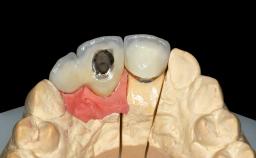

Replacement of Six Teeth with a Fixed Dental Prosthesis on Four Bone-Level Implants

In November 2010, a 44-year-old woman presented to the Harvard School of Dental Medicine seeking options to replace her failing six-unit conventional prosthesis. Having served for approximately 10 years, the fixed partial denture had repeatedly needed recementation after chronic dislodgement over the past few months. Following these episodes, the patient requested further evaluation of her current prosthesis and showed interest in exploring other options for a fixed solution. The patient was in good overall health, presenting with no systemic contraindications to implant therapy or any history of allergies; she did not smoke and was on no medications. Being a well-motivated individual, she regularly saw her general dental practitioner and effectively complied with oral hygiene requirements.